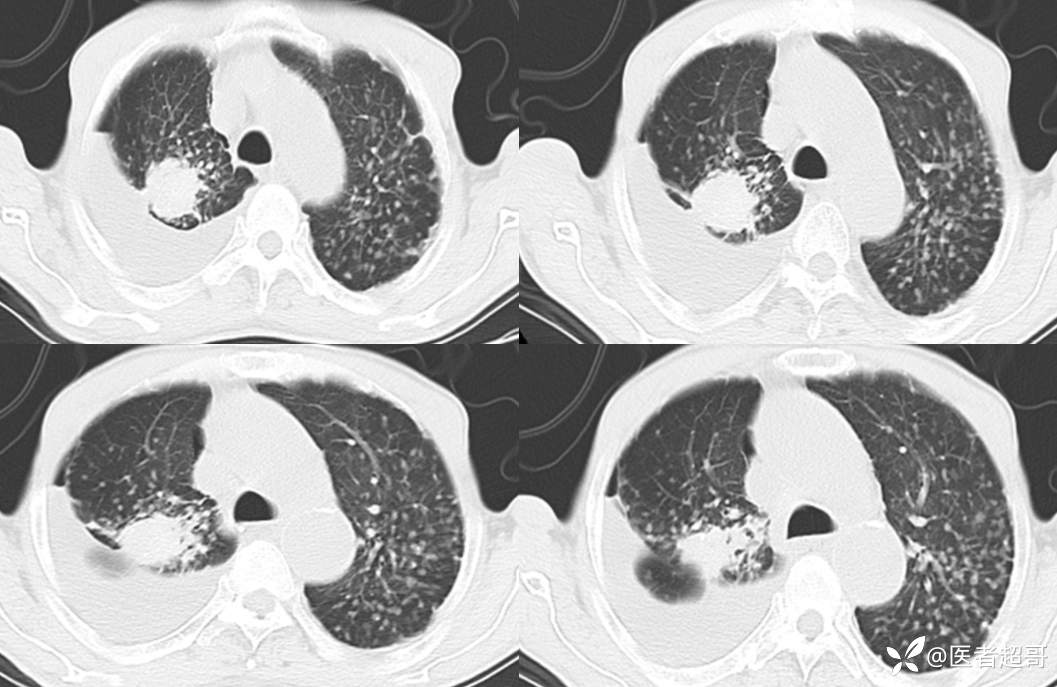

患者,男,72岁,农民,于2021年05月26日17时20分因"发作性精神行为异常10+天"入院。@丁香影像频道